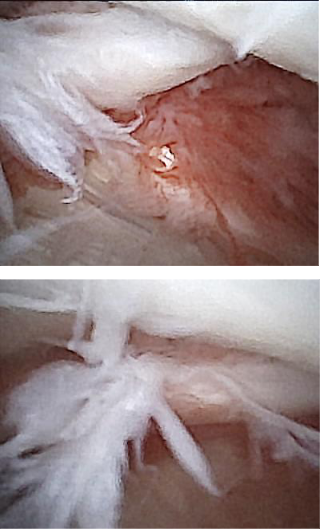

Some dogs, particularly active competitors or working dogs, strain the inside of their shoulder (the medial glenohumeral ligament, subscapularis tendon). The best way to make a diagnosis of medial shoulder instability is to perform minimally invasive arthroscopy and look inside the shoulder at the medial structures. Fortunately, Kansas City Canine Orthopedics can do this with a very small arthroscope (nanoscope) that provides excellent visualization and diagnosis. The images to the right show mild fraying and tearing of a medial glenohumeral ligament.